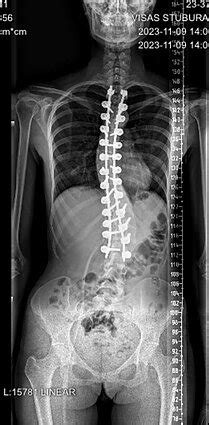

Vos pakliuvus į ligoninę, pirmieji atvažiavo keli draugai ir žurnalistai. Vėliau apie avariją sužinojo ir jo močiutė, su kuria Alanas gyveno Vilniuje. Pirmosiomis dienomis jam prireikė raminamųjų, kad nusloptų panika ir baimė. Jam buvo lūžęs vienas ir skilę du kaklo slanksteliai. Maždaug po mėnesio jau galėjo vaikščioti ir pats apsitarnauti, nes jam į kaukolę buvo įgręžtas Ilizarovo (Halo) aparatas. Jis atrodė kaip robotas, visas apžėlęs, su didžiule barzda. Mane operavęs chirurgas dr. Saulius Čepkus sakė, kad tai buvo pirmas Halo aparatas, pritaikytas galvai Lietuvoje. Tačiau, kaip vėliau paaiškėjo, jam šį aparatą nuėmė anksčiau laiko, nes jis sulūžo! Pagal planą turėjo nešioti aparatą ilgiau, bet naujo gydytojai nebedėjo. Alanas džiaugiasi, kad to užteko gydymui.

Mažai kas žino, kad metus trukęs jo gydymas ir reabilitacija po sudėtingos neurochirurginės stuburo operacijos, labai reikšmingai prisidėjo prie to meto medicinos studentų praktinių įgūdžių lavinimo. Tai buvo atvejis, kokį būsimi medikai galėjo pamatyti nebent vadovėlių iliustracijose - to meto Lietuvoje nebuvo galimybės praktikuotis su pacientu, patyrusiu tokio sudėtingumo stuburo traumą.